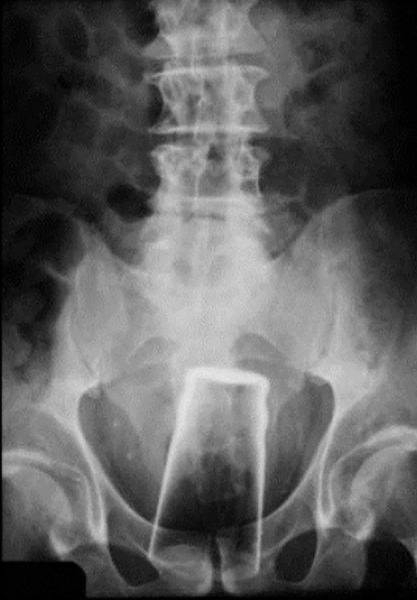

İÇİNDEKİ ŞEYE RÖNTGEN UZMANLARI ŞOK OLDU!

RÖNTGEN UZMANLARI ŞOK OLDU!

,Dünyada çekilen bu röntgenler hem röntgen uzmanlarını hemde görenleri şok ediyor...